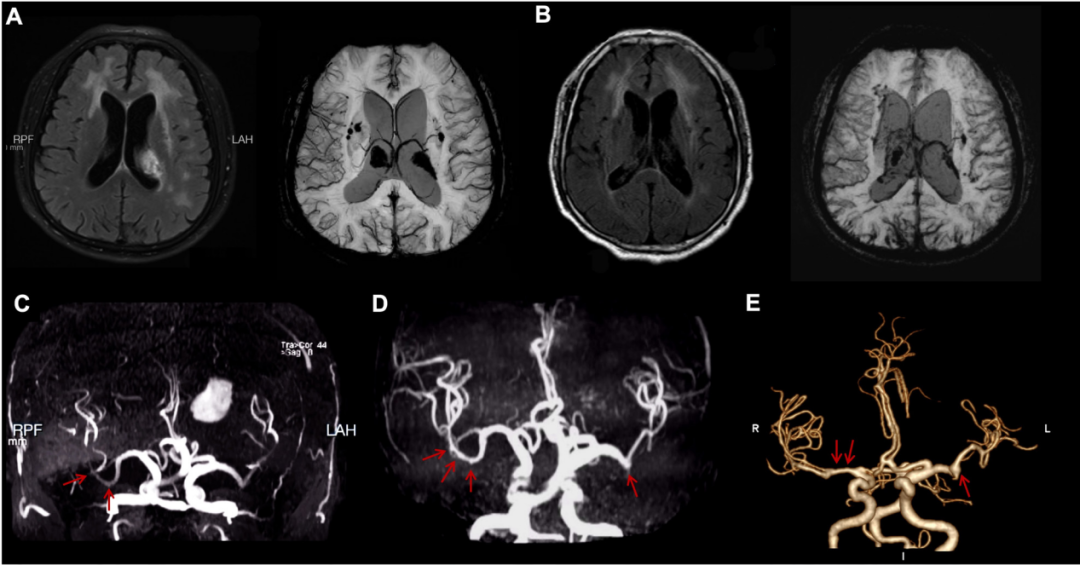

该团队在2026年1月份《Stroke》(中科院一区,IF = 8.9)杂志上报道了一例罕见的神经布鲁氏菌病相关脑血管病变。该研究通过动态影像学证据,首次完整展示了由布鲁氏菌感染引发的脑白质损害、脑出血及大脑中动脉串珠样扩张,经过抗感染治疗后呈现出动态改变。这一发现为感染相关脑血管病提供了全新的影像学表型,拓展了神经布鲁氏菌病的临床认知。齐鲁医院神经内科段若楠副研究员、高天宇医师为共同第一作者,赵玉英教授为通讯作者。